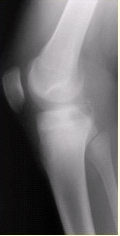

患者男,15岁。右膝X线平片和CT检查见下图。

此病变最可能的诊断是()

A.骨巨细胞瘤

B.内生软骨瘤

C.骨结核

D.成软骨细胞瘤

E.软骨黏液样纤维瘤

点击查看答案

本题答案:D

本题解析:暂无解析

根据此病灶内部多发钙化,对其定性诊断的提示是()

A.良性

B.骨源性

C.软骨源性

D.纤维源性

E.恶性

本题答案:C

病变发生部位是()

A.骨端

B.干骺端

C.骨骺

D.骨干

E.关节腔

对于此病变的征象,描述不正确的是()

A.右胫骨内侧平台近关节面下不规则溶骨性破坏

B.边缘可见硬化缘

C.病灶内可见多发细小点状钙化

D.可见骨膜反应

E.病变为偏心性生长